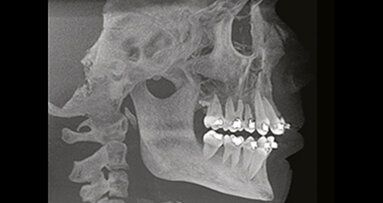

Úspěšné endodontické ošetření závisí na řadě faktorů, včetně správné instrumentace, úspěšné irigace a dekontaminace systému kořenových kanálků včetně apikálního zakončení a špatně přístupných oblastí jako jsou zúžení a postranní a vedlejší kanálky (obr. 1a, 1b).